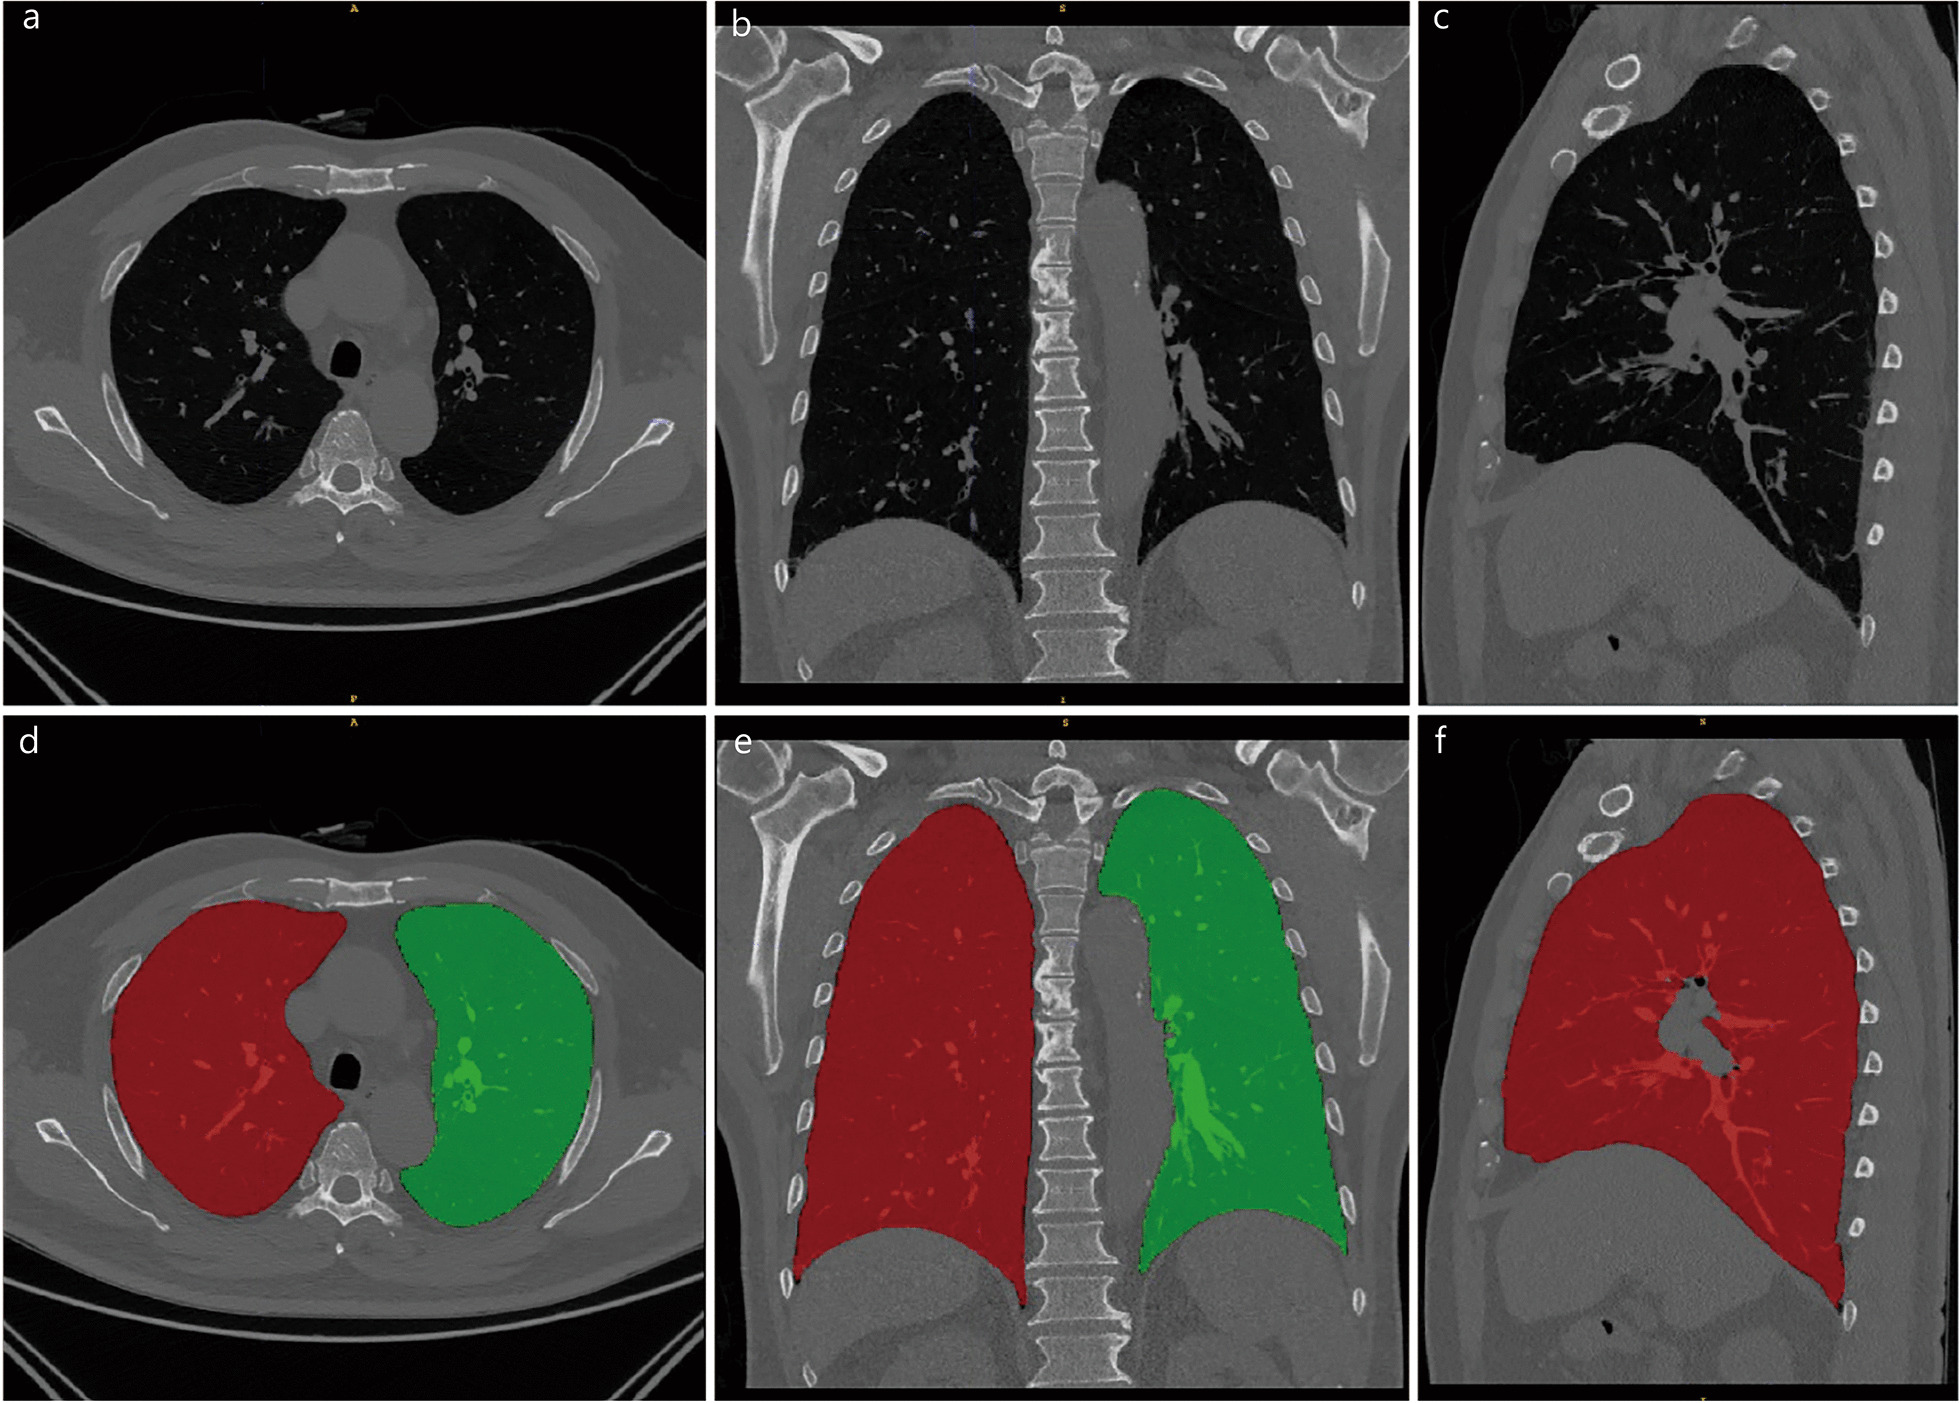

3. 两个典型病例

基于全肺 CT 影像组学列线图评估 COPD 风险的实际应用过程

左侧:非 COPD 患者案例

- a 图:45 岁女性的薄层胸部 CT 图像(横轴位),无明显肺气肿等异常表现。

- b 图:肺密度分析图,显示双肺均无肺气肿区域(无红色标注),提示肺结构基本正常。

- c 图:列线图评分结果。患者身高 152cm、不吸烟、影像组学评分(Radscore)为 - 2.08,结合年龄等因素,列线图总分为 44.8 分,对应 COPD 发病概率约 8.0%。肺功能检查显示 FEV1/FVC=0.8(≥0.7),符合非 COPD 诊断标准。

右侧:COPD 患者案例

- d 图:82 岁女性的薄层胸部 CT 图像(横轴位),可见弥漫性肺结构异常。

- e 图:肺密度分析图,双肺大部分区域被红色标注,提示广泛散在肺气肿改变。

- f 图:列线图评分结果。患者身高 152cm、不吸烟、Radscore 为 3.17,列线图总分为 48.2 分,对应 COPD 发病概率约 96.9%。肺功能检查显示 FEV1/FVC=0.6(<0.7),符合 COPD 诊断标准。